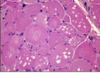

Distinct groups of atrophic and hypertrophic fibres in child w/ spinal muscular atrophy, hypertrophic fibres up to 100 micrometres

Atrophy restricted to darkly stained type 2 fibres induced by steroid therapy

ATPase staining following preincubation at pH 4.3 showing atrophy selectively affecting darkly stained type 1 fibres in a case of myotubular myopathy + hypertrophy of pale type 2 fibres